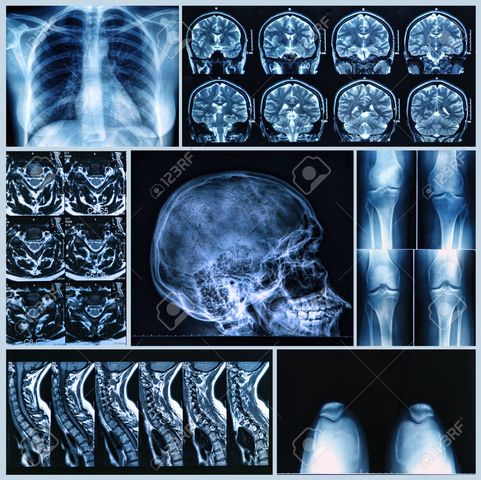

• Imágenes resonancia magnética

Imágenes resonancia magnética

Paul Lauterbur desarrolla las primeras imágenes de resonancia magnética (MRI). Utilización de imánes y ondas.